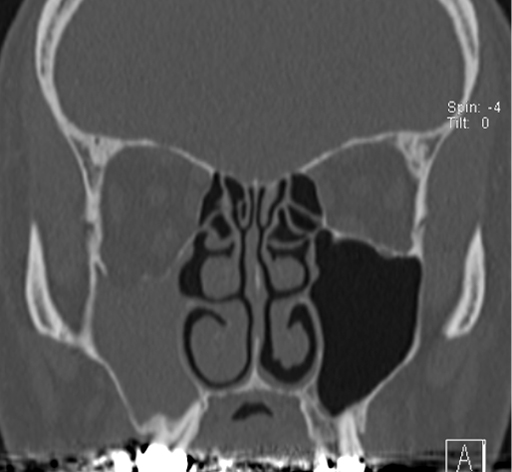

No.78症例2:61歳男性

約半年前より右眼奥の軽度鈍痛を自覚

今回、眼球下垂も自覚し、精査加療目的にて当院耳鼻咽喉科を受診した

3か月前に近医耳鼻科を受診、慢性副鼻腔炎の診断のもと約3カ月間マクロライド治療を受けるが改善なし

• 図1 CT冠状断像 骨条件表示